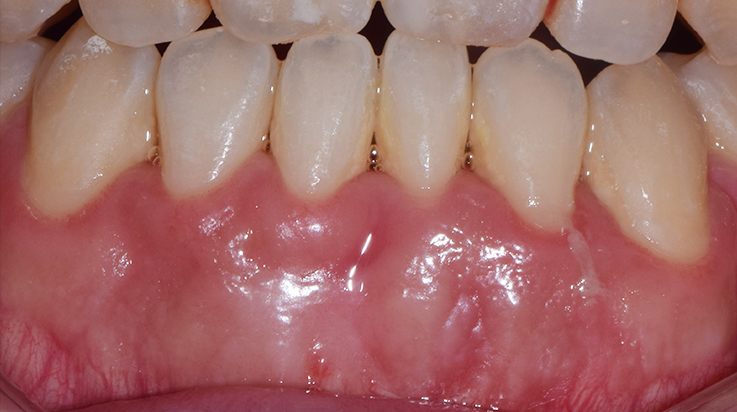

Clinical procedure increasing thickness of gingiva with soft tissue graft and collagen matrix